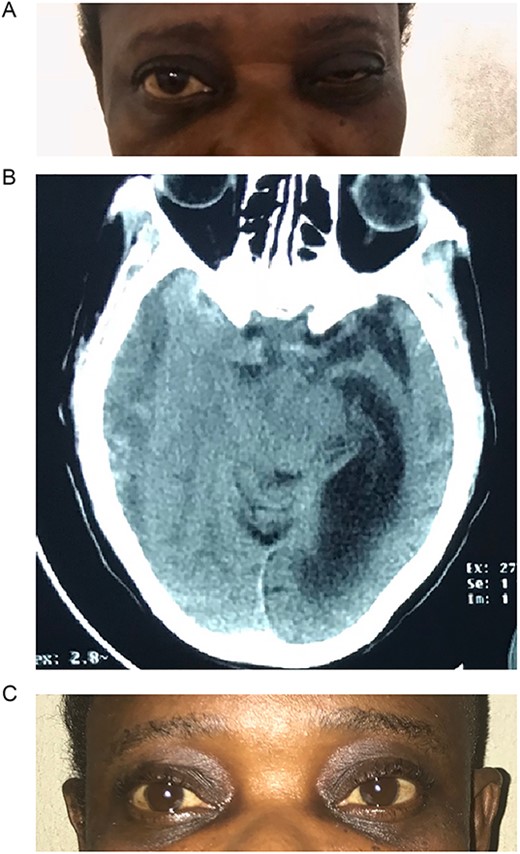

Case 1 – unilateral ptosis

A 42-year-old woman presented to the outpatient clinic with a 2-week history of headaches and 3-day history of drooping of the right eye and inability to open the eye. She had been involved in a passenger road traffic accident 3 weeks prior. At presentation she was fully conscious, and oriented in time, place, and person. However, she had a recent onset painless drooping of the right eyelid (Fig. 1A). Her vision was preserved with dilated pupils that reacted very slowly to light as well ophthalmoplegia. Other cranial nerves were normal on examination. There were no long tract signs.

(A) Pre-op with right ptosis/ophthalmoplegia. (B) Pre-op axial CT showing right CSDH. (C) Post op with resolution of ptosis.

Brain CT scan done revealed a right fronto-temporal CSDH causing uncal compression and midline shift as well as partial effacement of the ipsilateral lateral ventricle (Fig. 1B).

She underwent a right frontal and parietal burr hole drainage of the haematoma under local anaesthesia and sedation. Her post-operative course was satisfactory, and she was discharged on the 4th day post-surgery. She had complete resolution of her symptoms in 2 weeks (Fig. 1C).

Isolated third nerve palsy is extremely rare, with only ~16 cases reported in literature [16]. Of the 16 cases reported, one was associated with bilateral CNIII palsy after evacuation of CSDH. This was found to have resulted from pontine haemorrhage after the haematoma evacuation. Eleven of the 16 cases reported in literature had full recovery following surgery, 4 had partial recovery, and 1 did not recover. From a pathophysiologic standpoint, it is caused by direct compression of the right oculomotor nerve by the medial temporal lobe. During initial clinical evaluation, our patient was suspected of having right posterior communicating artery aneurysm. However, brain CT revealed a massive right-sided CSDH with uncal herniation and complete effacement of the basal cisterns (Fig. 1C). The oculomotor nerve was likely compressed by the uncus against the tentorial edge. The nerve is a mixed somatic and visceral motor nerve which innervates the levator palpebrae superioris and the extraocular muscles except the lateral rectus and the superior oblique muscles. It also carries parasympathetic fibres to the pupillary constrictors and the annular portion of the ciliary muscle. Pressure on the oculomotor nerve can cause paralysis of the levator palpebrae muscle (ptosis), pupils that are non-reactive to light and restricted eye movement as described in our patient.